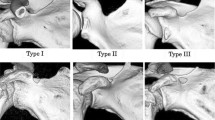

The suprascapular notches were classified according to Polguj et al. (2011). In this classification, types IV (suprascapular opening) and V (discreet notch) are recognized based on visual assessment. Types I–III were assigned based on measurements of maximal width (MW: distance between the most distant points of the upper edge of the SSN) and maximal depth of the SSN (MD: imaginary line between the level of the MW and the deepest point of the SSN) (Fig. 1). Maximal width (MW) is 0.5 mm less than the maximal depth (MD) in type I (MW < MD), equal to MD in type II (MW = MD), and 0.5 mm greater than MD in type III (MW > MD).

Among all 346 scapulae, type V (in 225 scapulae; 65.0 %) and type III (in 114 scapulae; 32.9 %) SSNs were most common. Types I and II were present in 5 (1.4 %) and 2 (0.6 %) scapulae, respectively. Figure 2 shows the representative cases of SSN types I–III.

The different SSN type distribution between children and adults and the positive correlation between age and SSN size suggest that the final shape of the SSN develops with age. It should be noticed that pediatric type V SSN presented a more heterogeneous morphology than the adult type V because of the presence of the tubercle on the superior border of the scapula, which was observed in 16 cases. Hence, in children, the type V SSN should be subdivided into types Va and Vb based on the respective absence or presence of this tubercle (Fig. 2). In this sense, type Vb (“type V with tubercle”) may represent a transient form between juvenile type V of the SSN and the adult type of a different kind.